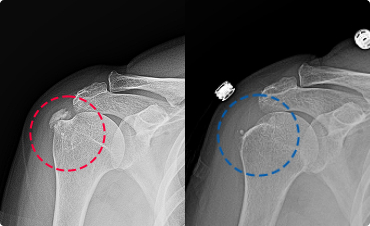

석회건염이란?

어깨 힘줄(회전근개) 내부에 석회가 침착되면서 갑작스러운 극심한 통증과

팔을 들어 올리기 어려운 기능 제한이 발생하는 질환 입니다.

초음파 유도하 석회 융해 및 흡인술[Calcific-Clear]

고해상도 초음파로 석회의 위치와 크기, 단단함을 실시간으로 확인하며 정확히 조준합니다.